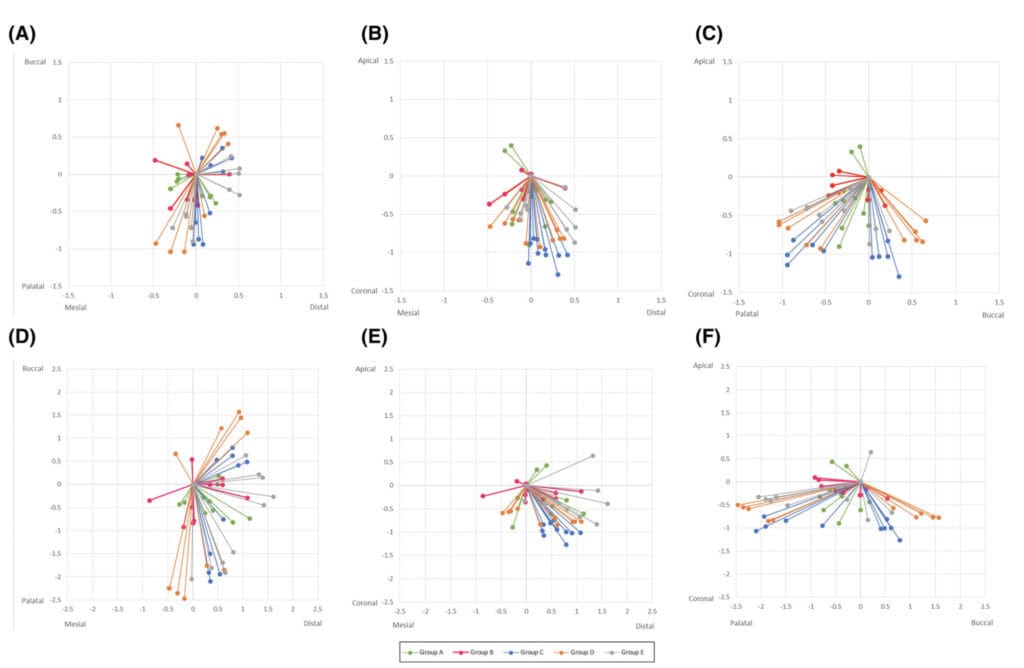

With regards to precision now, one would have to utilize simulation studies analysing the distribution of the deviations in repeated implant placement using the same workflow as we used in the clinical studies above.

In a simulation study with multiple placements, the deviations of each placement ideally should be scattered equally around the optimal centre, like a symmetric firework. In reality however deviations tend to cluster more towards some sides, pointing to some systemic influence mostly attributed to the operator such as right- or left-handed, ergonomics, optical field as well as specific anatomic locations of the implant site and more. How much clustering of the deviation is acceptable and when should we seek and correct the systemic influence? Well, this is a wider discussion and it should be always be seen in conjunction with the accuracy readings. Maybe we can discuss this in more detail in the future.

The image below is from one of our simulation studies and it shows the clustering of the deviations (precision) for the standard level of accuracy. As you can see, although not too bad, our firework looks like it was fired on a very windy day in some instances…! To understand more why this happens however, you will have to read the paper!